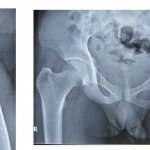

Image Challenge, #Hip Trauma

Popular Answer may not imply right answer Follow our twitter handle for the right answer, www.twitter.com/drhiteshg